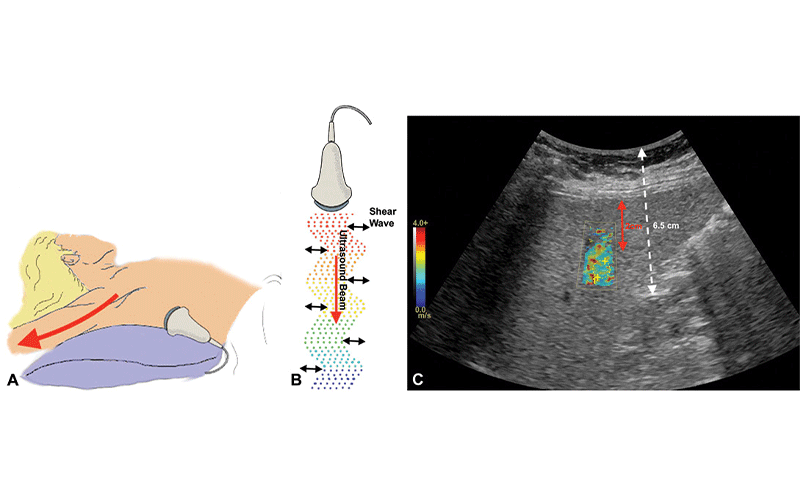

Patient positioning and principles of two-dimensional shear-wave elastography. A, Patient’s right arm should be placed in maximal abduction to permit probe placement and to increase intercostal space to reduce rib shadowing. Right side is preferentially chosen; left-sided measurements are often artifactually increased due to secondary compressive effects of the probe, heart, or stomach. B, Standard curvilinear transducer, typically used for abdominal imaging applications, is used to generate focused ultrasound energy, resulting in shear waves traveling perpendicular to ultrasound pulse. High-quality B-mode imaging is used to track shear waves and to measure propagation speed (shear-wave velocity), which correlates to liver stiffness. C, Color-coded elastogram scale is superimposed on B-mode US images and suitable region of interest (ROI) is placed to measure liver stiffness. ROI should be positioned at least 1.5–2 cm away from liver capsule (arrow in C) in a site free traversing vasculature, on image without rib shadowing artifact, and not more than approximately 6.5 cm from skin surface.

O’Shea, et al, Radiology 2021 ©RSNA 2021